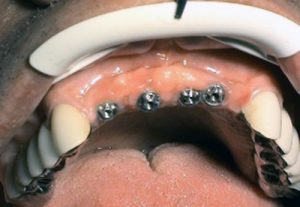

– "teeth in one day"- "all in one" – implantation and

provisional prosthetics during one day

– "all on four"

"all on six" – implant solution concept for complete

tooth loss of upper or lower jaw supported by four or six

implants